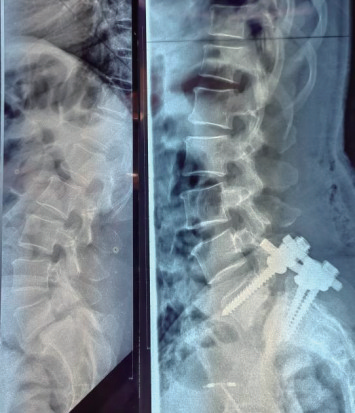

第三阶段 独立操作。经过前两阶段扎实训练及超过50台手术的实践,当地团队技术日趋熟练。最终,他们实现了TLIF手术的完全独立开展。2025年10月15日,首例由尼日尔本地医生团队完全独立主刀的TLIF获得圆满成功(表1及图3)。

图3 术前术后影像学比较显示腰5滑脱复位满意、内固定稳定